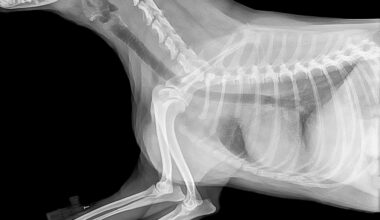

Laser therapy has multiple applications within veterinary rehabilitation, targeting both acute and chronic conditions in pets. This treatment is beneficial for situational injuries, such as strains, sprains, and surgical recoveries, promoting faster healing while minimizing pain. Additionally, its effectiveness extends to chronic issues like osteoarthritis and hip dysplasia, common in aging pets. Pets suffering from these long-term conditions experience relief from discomfort, allowing them to regain mobility and improve their overall quality of life. Furthermore, laser therapy can assist in treating various dermatological issues, including hotspots and wounds, promoting faster healing and reducing inflammation through its regenerative properties. The versatility of laser therapy makes it an attractive option for holistic treatment approaches, especially for pets requiring multiple therapies. As with any therapeutic intervention, it is vital to have a thorough veterinary assessment to tailor treatments specifically to the individual needs of each pet. This personalized approach ensures that the chosen laser therapy program aligns with the overall rehabilitation goals, resulting in optimal recovery outcomes and improved pet health.

Veterinarians focus on specific protocols when employing laser therapy to achieve maximum benefits for pets. Each treatment session typically lasts between five to twenty minutes, depending on the area being treated. The frequency of sessions varies based on the severity of the pet’s condition, with some requiring several visits per week. Over time, owners will likely witness gradual improvements as pain alleviates and mobility increases. During treatments, veterinary professionals use laser devices designed for veterinary applications, ensuring proper settings for different conditions. The light emitted during laser therapy penetrates through the skin, stimulating cellular activity and promoting healing without causing discomfort. Owners often report their pets appearing relaxed during sessions, which can significantly relieve anxiety associated with veterinary visits. Furthermore, educational materials and demonstrations help pet owners understand the benefits of laser therapy, allowing them to feel confident in their choice of rehabilitation for their pets. The importance of maintaining communication with the veterinary team enables owners to adapt treatment plans based on their pets’ responses, further enhancing the effectiveness of laser therapy and contributing to better health outcomes.